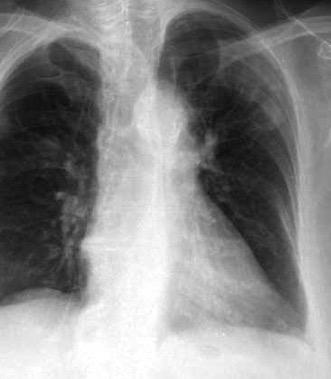

Neumonía a neumococos base izda. con derrame que aumenta.

Broncograma en lateral y en US.

(36-66% en ingresados)